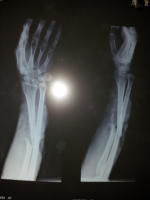

Xrays-Right hand arm Ap/Lateral

Xray shows open fracture of right radius.